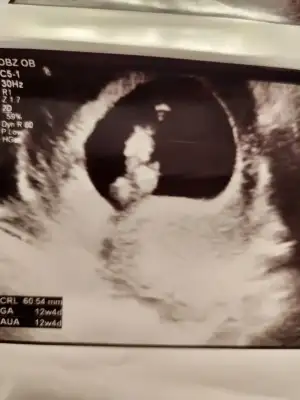

Kızlar dün doktor birkaç tane ultrason fotoğrafı vermişti. Birisi bu. Bu neresi acaba neyi gösteriyor hiç anlamadım fikri olan var mı

Eklentiler

• 1000072236.webp

1000072236.webp

20,4 KB · Görüntüleme: 58